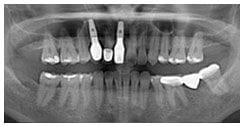

X 光片

術後X光片